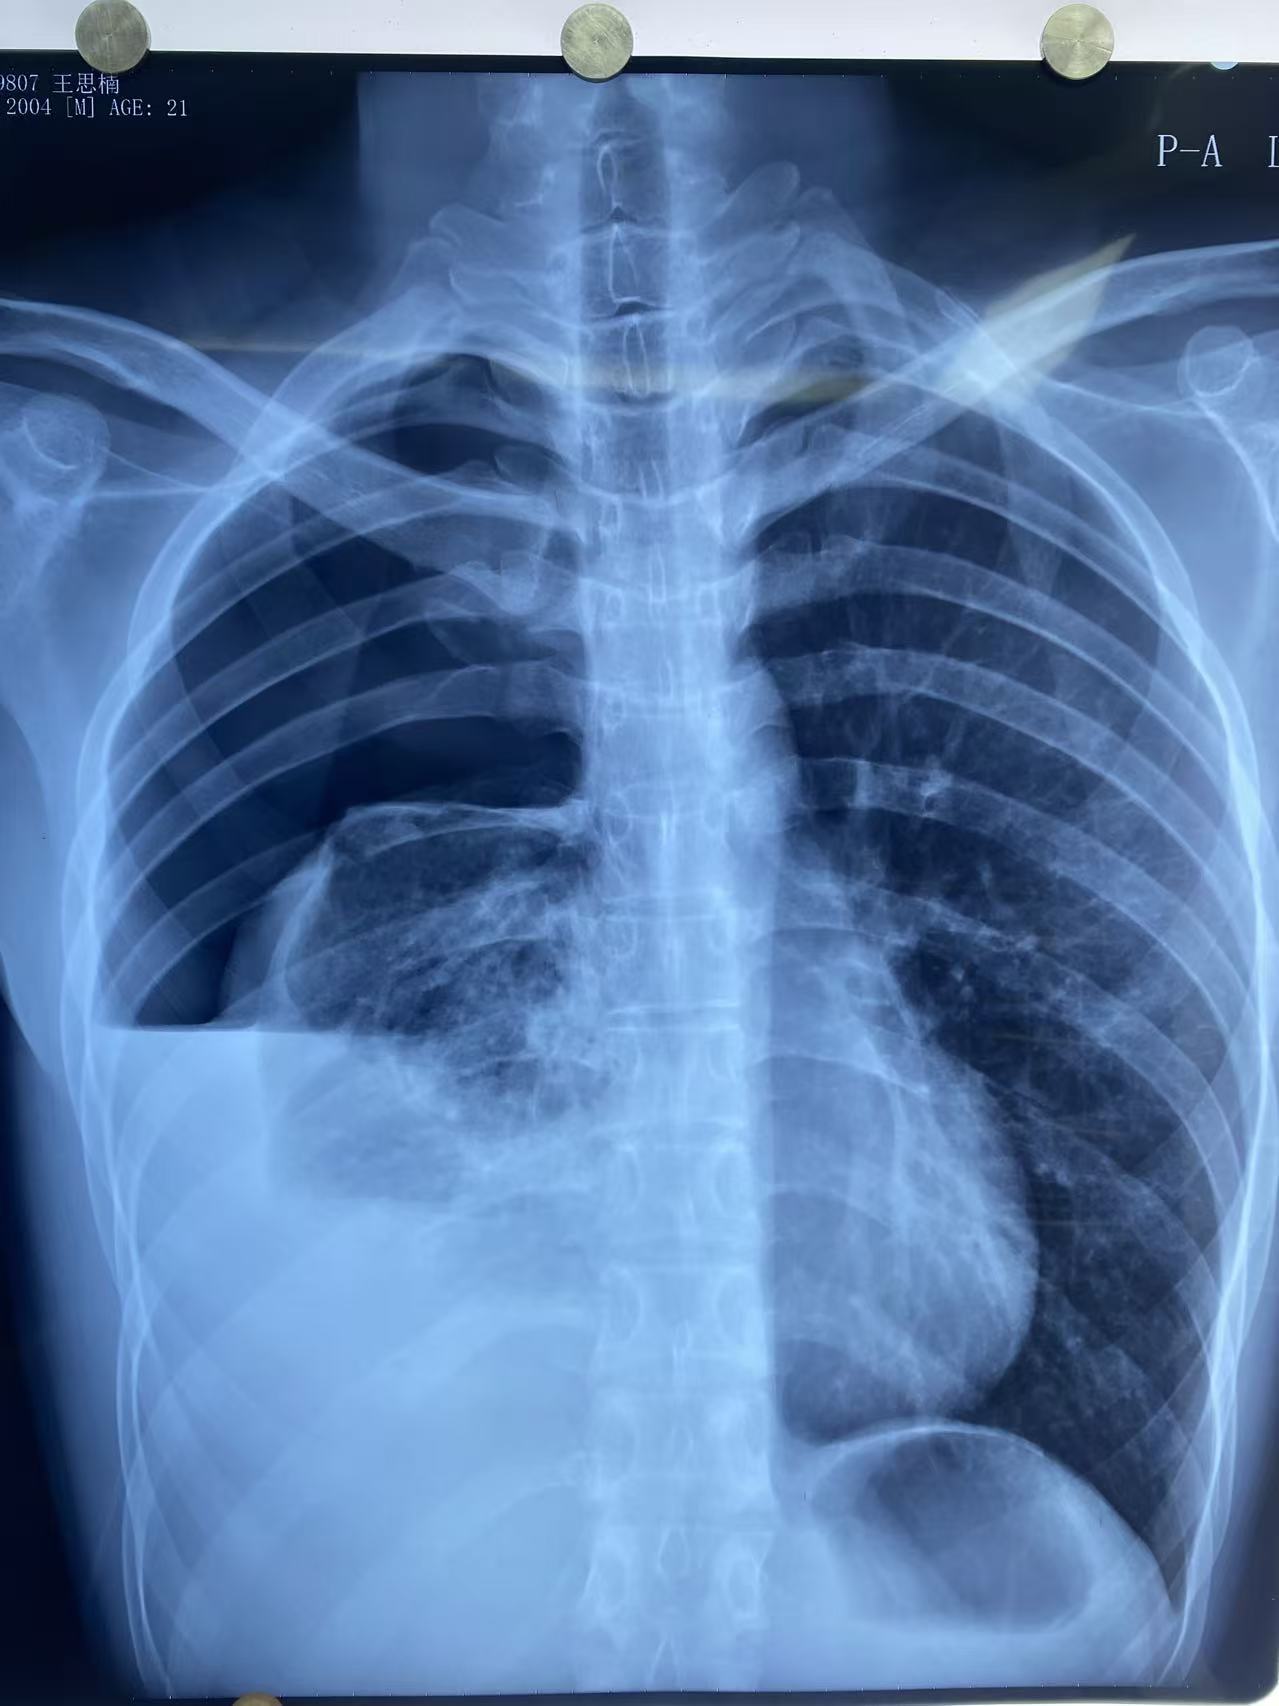

21岁的小王正值大四,一天前日常活动后突然觉得右侧胸闷、呼吸困难,伴右侧胸痛,休息后自觉缓解。第二天患者自觉胸痛及胸闷症状明显加重,校医院胸部X线片提示右侧液气胸,右肺压缩大于80%(如图1),属于典型自发性血气胸。患者经由120紧急送至清华大学附属垂杨柳医院急诊。此时,患者大汗,贫血貌,胸痛无法平卧,胸外科主治医师赵云会诊并请示胸外科主任崔健,明确诊断为右侧血气胸。需尽快手术治疗。

▲图一